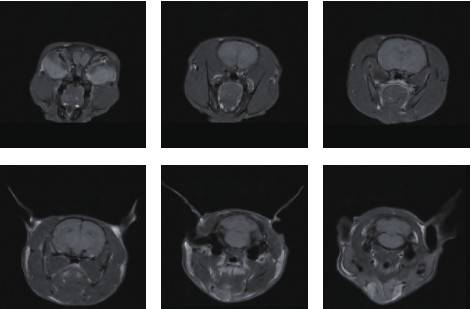

小鼠頭部成像